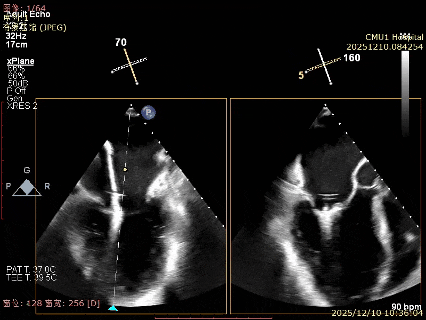

为了避免长时间TEE对食道造成损伤,术前即刻3D-TEE短时进一步明确二尖瓣病变相关解剖情况。

术前Bi-com

3D-TEE二尖瓣相关解剖学参数:后叶长度:22-25mm,前叶长度:31-34mm;瓣环AP径:47mm,ML径:48mm;瓣口面积:约7.8cm²;脱垂宽度:30mm,最大连枷间距:14mm。

术前即刻TEE进一步明确了二尖瓣反流的机制(DMR)及反流程度(5+),重点完善了病变区域二尖瓣解剖结构的评估,预估手术难点/影响手术效果的解剖结构为冗长的二尖瓣后叶(PML约25mm),宽大的脱垂(Flail Width约30mm),超大的连枷间距(Flail gap约14mm)。